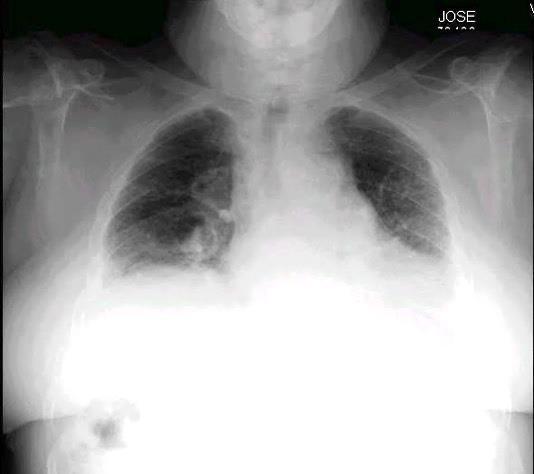

Pliegue axilar Normal

Rehúsa cirugía

2011. Acude por masa axilar

Linfoma NH de cél. B. Invasión Transtorácica.

Afectación axilar